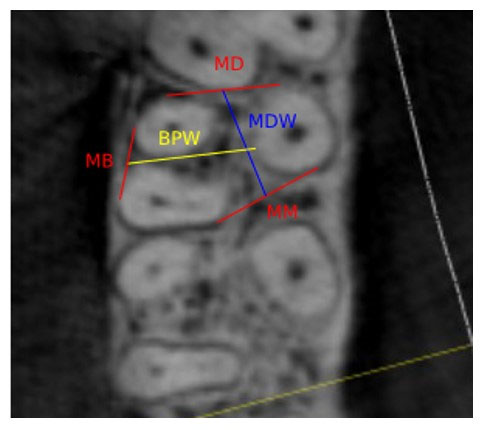

Using axial images, IRS widths were recorded both mesiodistally and buccopalatally at three levels, i.e., crestal widths at 0.5 mm apical to the furcation, apical widths recorded at 0.5 mm coronal to a line connecting the apices of the two shortest roots, and middle level measurements taken at the mid-point between the other two measurement levels (Figure 1).

Figure 1.

(a) A crestal measurement was recorded 0.5 mm apical to the molar furcation. (b) An apical measurement was recorded 0.5 mm coronal to the line connecting the apices of the two shortest roots. (c) A middle measurement was recorded midway between the crestal and apical levels; (d), (e), and (f) show the axial views of the same points corresponding to a, b, and c, respectively (MB: mesiobuccal, DB: distobuccal, P: palatal).